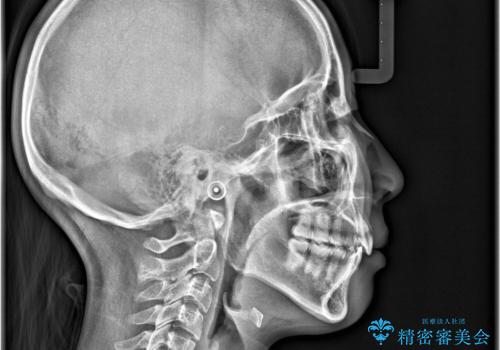

- 前歯が出ていることと、下の歯のがたがたで歯磨きがしにくいことを主訴に来院されました。

マウスピース矯正の希望があり、ワイヤーリカバリの可能性を伝えたうえでインビザライン抜歯矯正を行っています。

来院が途中途絶えたこともあり、4年ぐらい期間がかかりましたが、インビザラインだけで治療を終えることができました。